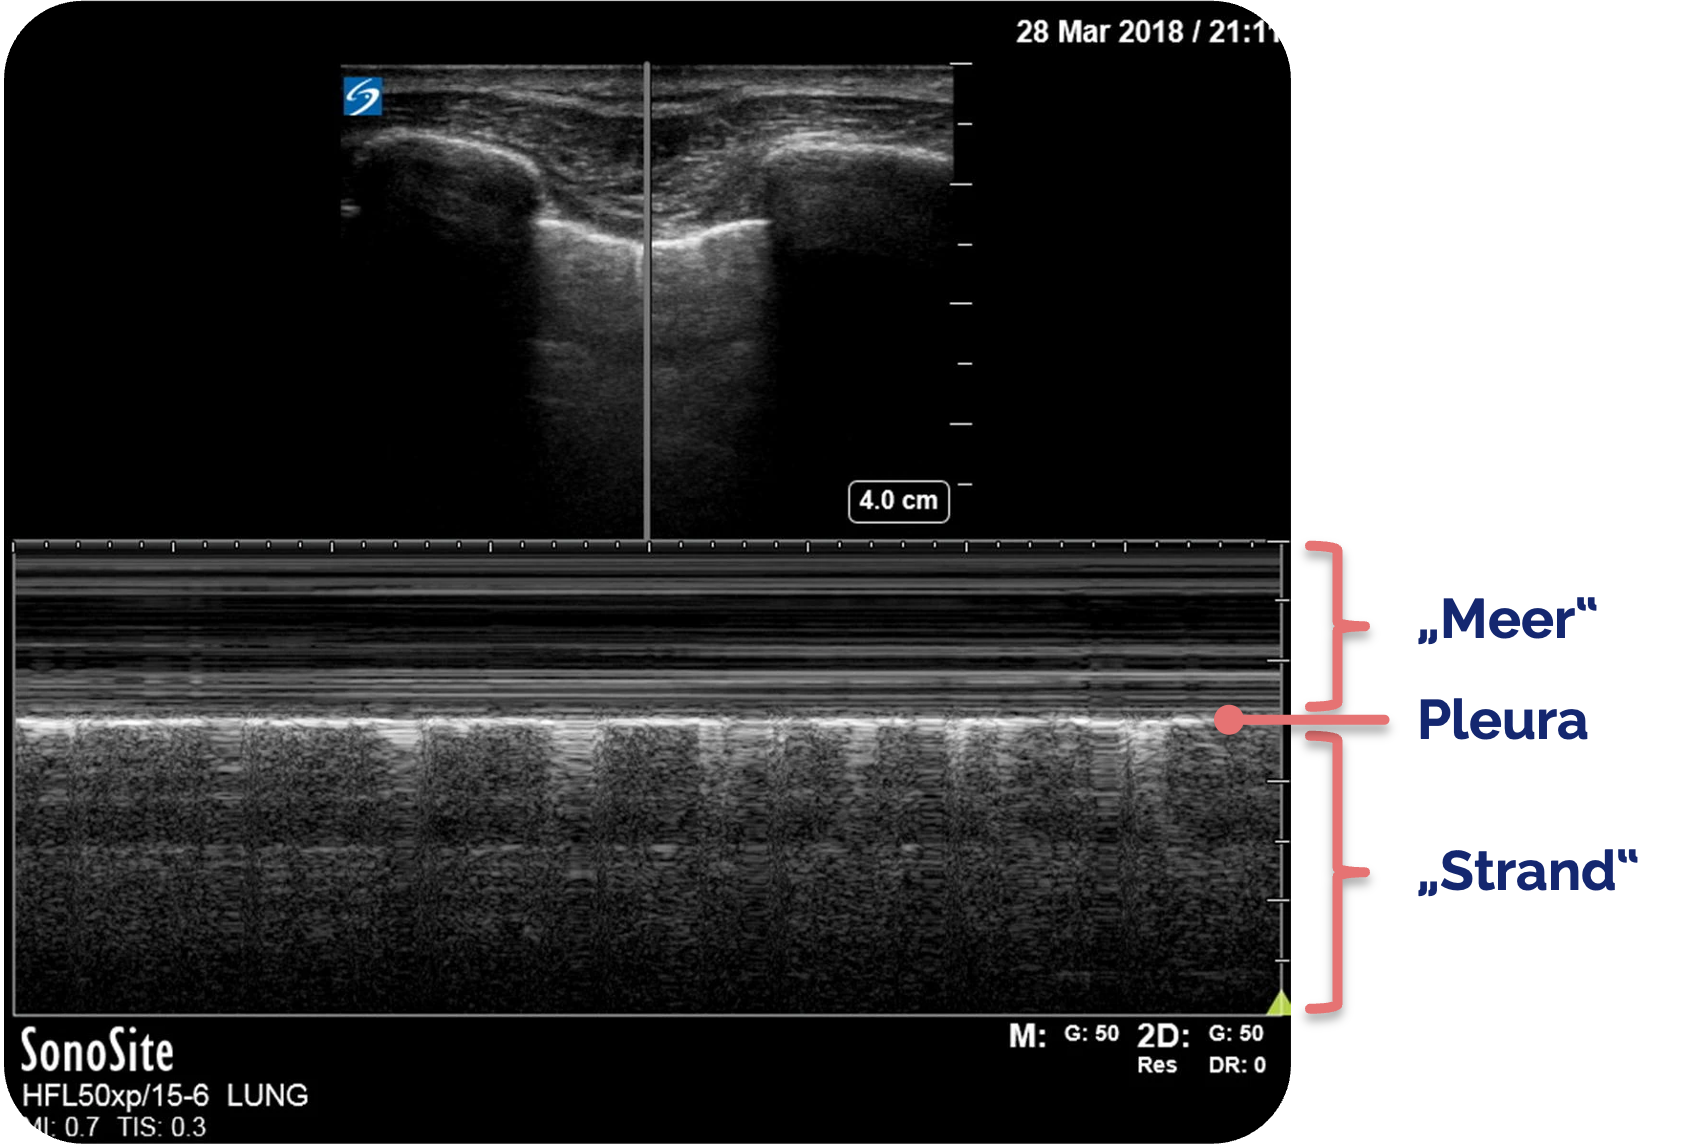

Normalbefund im M-Mode :

Wenn eine Darstellung des Pleuragleitens erschwert oder unsicher ist, ist der M-Mode

Im oberen Bereich des M-Mode

Figure 5 aus Ketelaars, R., Reijnders, G., van Geffen, GJ. et al. ABCDE of prehospital ultrasonography: a narrative review. Crit Ultrasound J 10, 17 (2018). https://doi.org/10.1186/s13089-018-0099-y. Teilausschnitt des Originalbilds. Es wurden die Markierungen und Beschriftungen ergänzt.

Auch beim M-Mode

Der M-Mode

Das Strandmuster kann überstrahlt oder zu schwach dargestellt werden. Hier hilft eine Überprüfung der Einstellungen. Ein voreingestellter eFAST